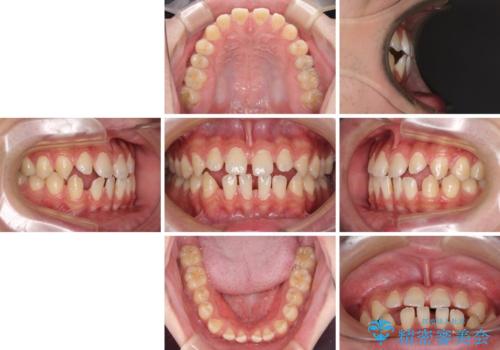

- 上下前歯の隙間を気にして来院された患者様です。

飲み込みや話をするときに舌を突出させる癖が強くあり、それが原因でスペースが空いていました。

舌癖を改善するためのトレーニングを行いながら、ワイヤー装置を用いて前歯の隙間を閉じていくこととしました。